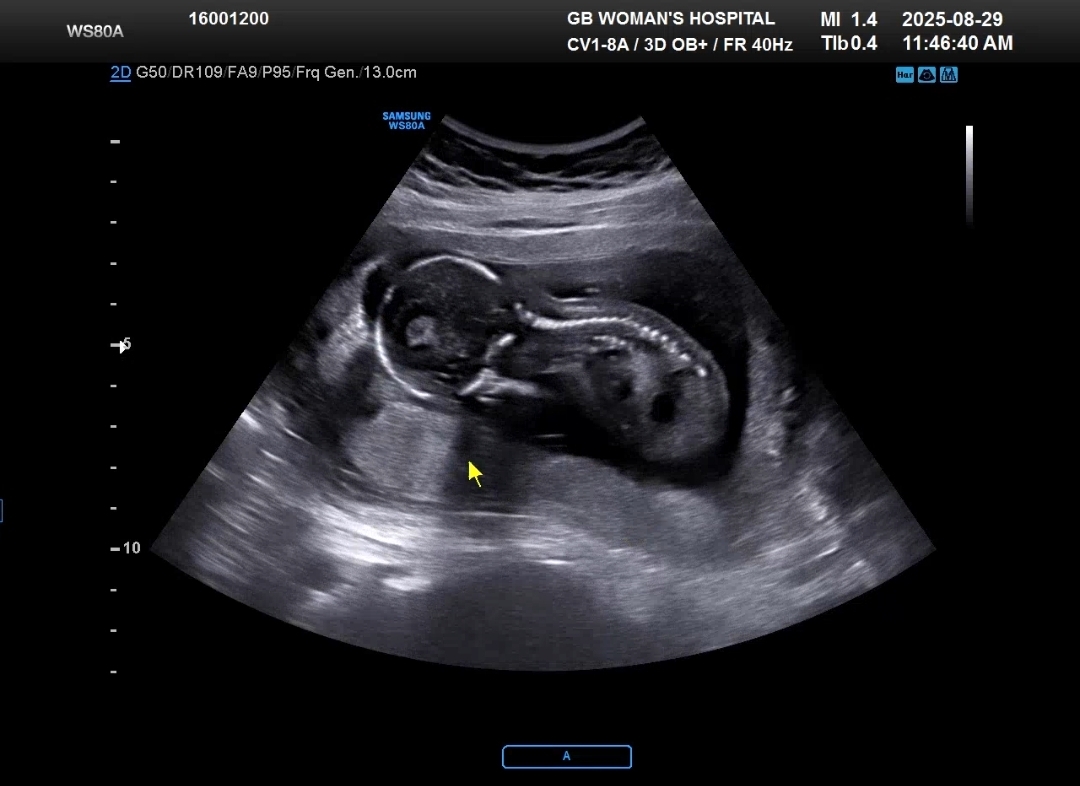

나는 15주 6일!! 내 생일에 병원을 방문했다.

먼저 진료를 보러가서 4주만에 본 뽀별이는 척추뼈도 이제 선명하게 보이고

훌쩍 커있었다!! 이제는 초음파에 한눈에 안 담길만큼 커진 모습~~ 💕

머리크기, 머리둘레, 배둘레, 허벅지뼈길이 등으로 현재 크기를 가늠했고

160g이라는 뽀별이!!ㅎㅎ 너무 조그맣다

아 그리고 드디어 나온 성별은 딸~~